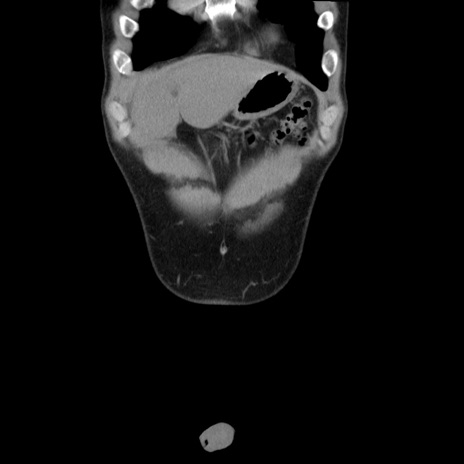

症例36(冠状断像)

【症例】20歳代 男性

【主訴】心窩部痛

【現病歴】今朝より上腹部痛あり。一旦軽快していたが再度出現したため救急要請。昨日夕に白身の魚を含む刺身を食べた。

【身体所見】BP 136/89mmHg、HR 74/min、BT 37.0℃、腹部:膨満、軟、心窩部に圧痛あり。反跳痛なし、筋性防御なし、腸雑音やや亢進あり。

【データ】WBC 17700、CRP 0.48